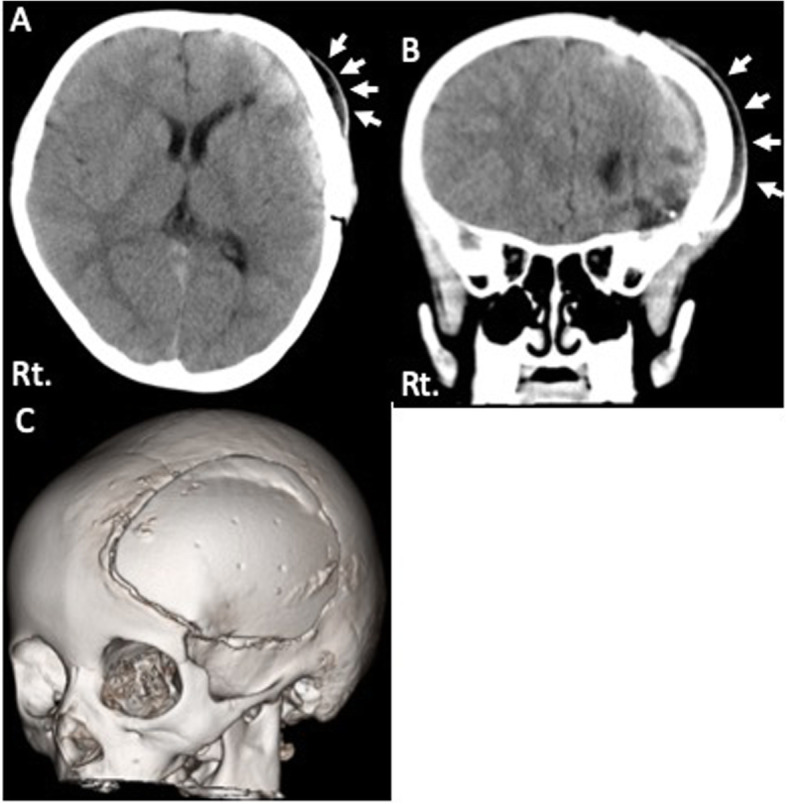

Head computed tomography (head CT) showed the fluid collection under the scalp and epidural space [Fig. 2]. The CT Hounsfield number of this lesion was low; this finding was suggesting the collection of cerebrospinal fluid rather than that of bleeding. We speculated that the cerebrospinal fluid leakage had occurred due to a dural laceration at the previous surgical site. We decided to surgically repair this lesion based on our speculation.

Fig. 2.

Radiological examination after head injury. a, b Head CT showed subcutaneous fluid collection (white arrows). c Three-dimensional image showed the relationship between the artificial bone flap and skull. No obvious deviation of the bone flap